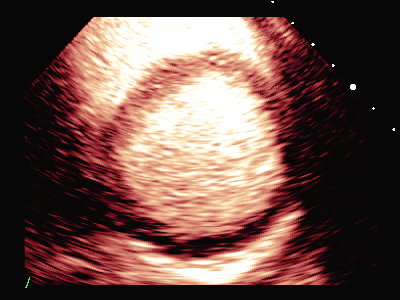

负荷前左室壁未见明确节段性运动异常,左室各节段心肌灌注充盈良好。

平板负荷量达89%时,该时患者心率157次/分,出现短阵性室性心动过速,即刻超声造影检查显示:负荷后左室前间隔中段、室间隔心尖段、侧壁中段、心尖段、下壁心尖段、前壁心尖段及心尖帽运动减弱。室间隔心尖段及心尖帽心肌灌注稀疏。

患者休息后检查:左室壁未见明确节段性运动异常,左室各节段心肌灌注充盈良好。